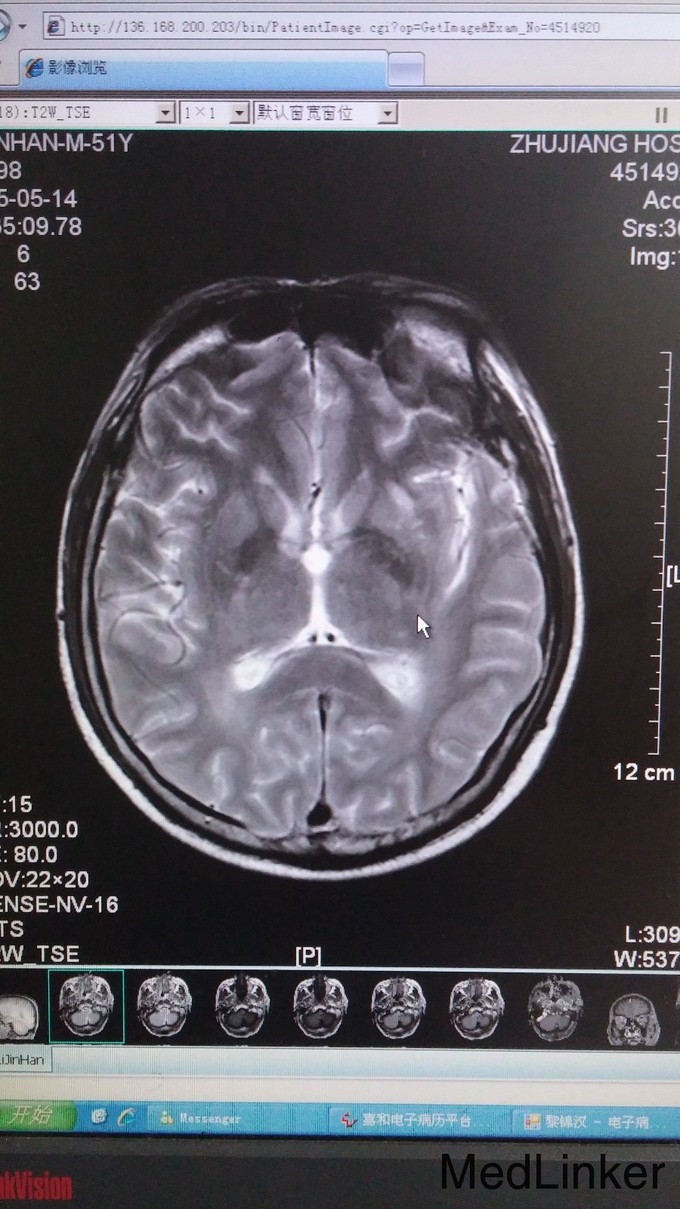

神志昏睡、语无伦次,定向力、判断力正常、计算力、记忆力无法检查。左侧肌张力增高。四肢肌力2级。指鼻、跟膝胫试验检查不配合。双侧腹壁反射存在。双侧肱二头肌、肱三头肌、膝腱、跟腱反射减弱。颈抵抗,颏胸距3横指,Kernig和Brudzinski征阴性。辅查: 1. 血常规:HSCR 3.24mg/L,白细胞计数9.1G/L,中性粒细胞计数8.32G/L,中性粒百分数91.4%;CK 504IU/L, CK-MB 27.9 IU/L, LDH 293 IU/L; 2. 腰穿:脑压225mmH20,氯119.9mmol/L,葡萄糖5.5mmol/L, 乳酸4.7 mmol/L, 蛋白1460 mg/L, 白细胞 60M/L 3. 颅脑MRI:双侧大脑半球(基底节区及放射冠区分布较多)、小脑、桥脑、中脑、延髓多发异常信号灶,增强扫描颅内血管明显增多、迂曲,脑膜增厚强化,可符合播散性脑脊髓炎改变,不排除其内白质疏松及腔隙性脑梗塞因素。肌电图:神经性受损(运动神经为主);脑电图:轻-中度异常脑电图;胸片示:下肺野纹理增粗、模糊,不排除炎症。